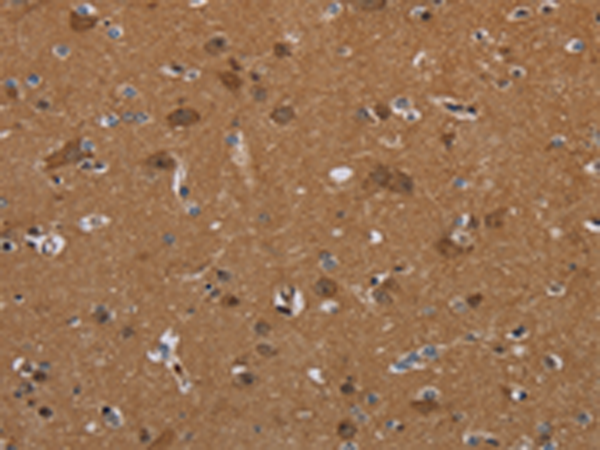

分类: 科研抗体货号: P05023别名: LOR2; WS9-14应用: IHC反应种属: Human, Mouse, Rat